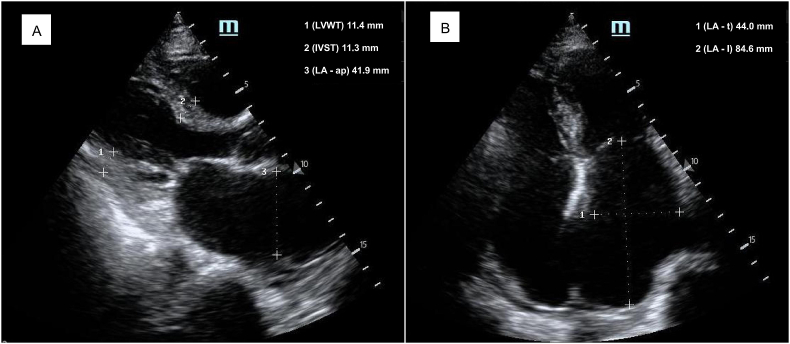

Acute organ dysfunction in older patients is often a continuation and exacerbation on the basis of chronic degeneration or injury [10]. In this study, the HFHFS group had more chronic heart disease preoperatively, while the significant association between HFHFS and postoperative cardiac dysfunction was also confirmed by subsequent multivariate regression analysis. Changes in the structure and function of the heart complicate fluid treatment after bleeding, making it no longer a simple matter of “loss and supplement”. Figure 4 shows images of bedside cardiac ultrasound of a 85-year-old woman with hypertension who developed HFHFS 20 h after surgery, where significantly enlarged left atrium indicates increased left ventricular filling pressure. Intravenously infused fluid may become congested in the pulmonary or even systemic circulation, while the left ventricle with diastolic filling restrictions has difficulty obtaining and accommodating effective blood volume. This patient developed acute heart failure characterized by the coexistence of congestion and hypoperfusion after surgery. Similar findings are not uncommon in senile hip fracture patients (especially those with hypertension and atrial fibrillation), but the clinical presentation of cardiac dysfunction may vary by reason of differences in the severity of congestion and hypoperfusion [22]. Delirium, as a sign of acute brain dysfunction, has been extensively studied, but its mechanism remains difficult to fully clarify. Perioperative BP is closely related to postoperative delirium, in which intraoperative and postoperative hypotension and increased BP fluctuations all contribute to delirium development [20,23,24]. Our observations showed the same results. Furthermore, heart failure itself plays an important role in the development of delirium in patients with cardiac dysfunction [25]. Finally, although the findings of the study showed no association between HFHFS and postoperative renal dysfunction, we presume that this may be an uncertain conclusion. Because of the reduction in muscle mass and the prevalence of chronic kidney disease, the rate and magnitude of increase in serum creatinine levels may be attenuated in older patients who develop acute kidney injury [26]. We may therefore have underestimated the incidence of postoperative renal dysfunction, and the relationship between HFHFS and postoperative renal dysfunction needs further investigation. The presence of hypotension as well as vital organ dysfunction complicated postoperative management, which inevitably led to a significantly prolonged length of hospital stay.

Figure 4.

Bedside cardiac ultrasound images of a patient with HFHFS. A 85-year-old woman with hypertension developed HFHFS 20 h after surgery. The enlarged atria suggest preoperative chronic changes of the heart, which may contribute to HFHFS and subsequent acute cardiac dysfunction. A, Parasternal long-axis view; B, Apical four-chamber view. Abbreviations: LVWT, left ventricular wall thickness; IVST, interventricular septal thickness; LA-ap, left atrial anteroposterior diameter; LA-t, left atrial transverse diameter; LA-l, left atrial length.